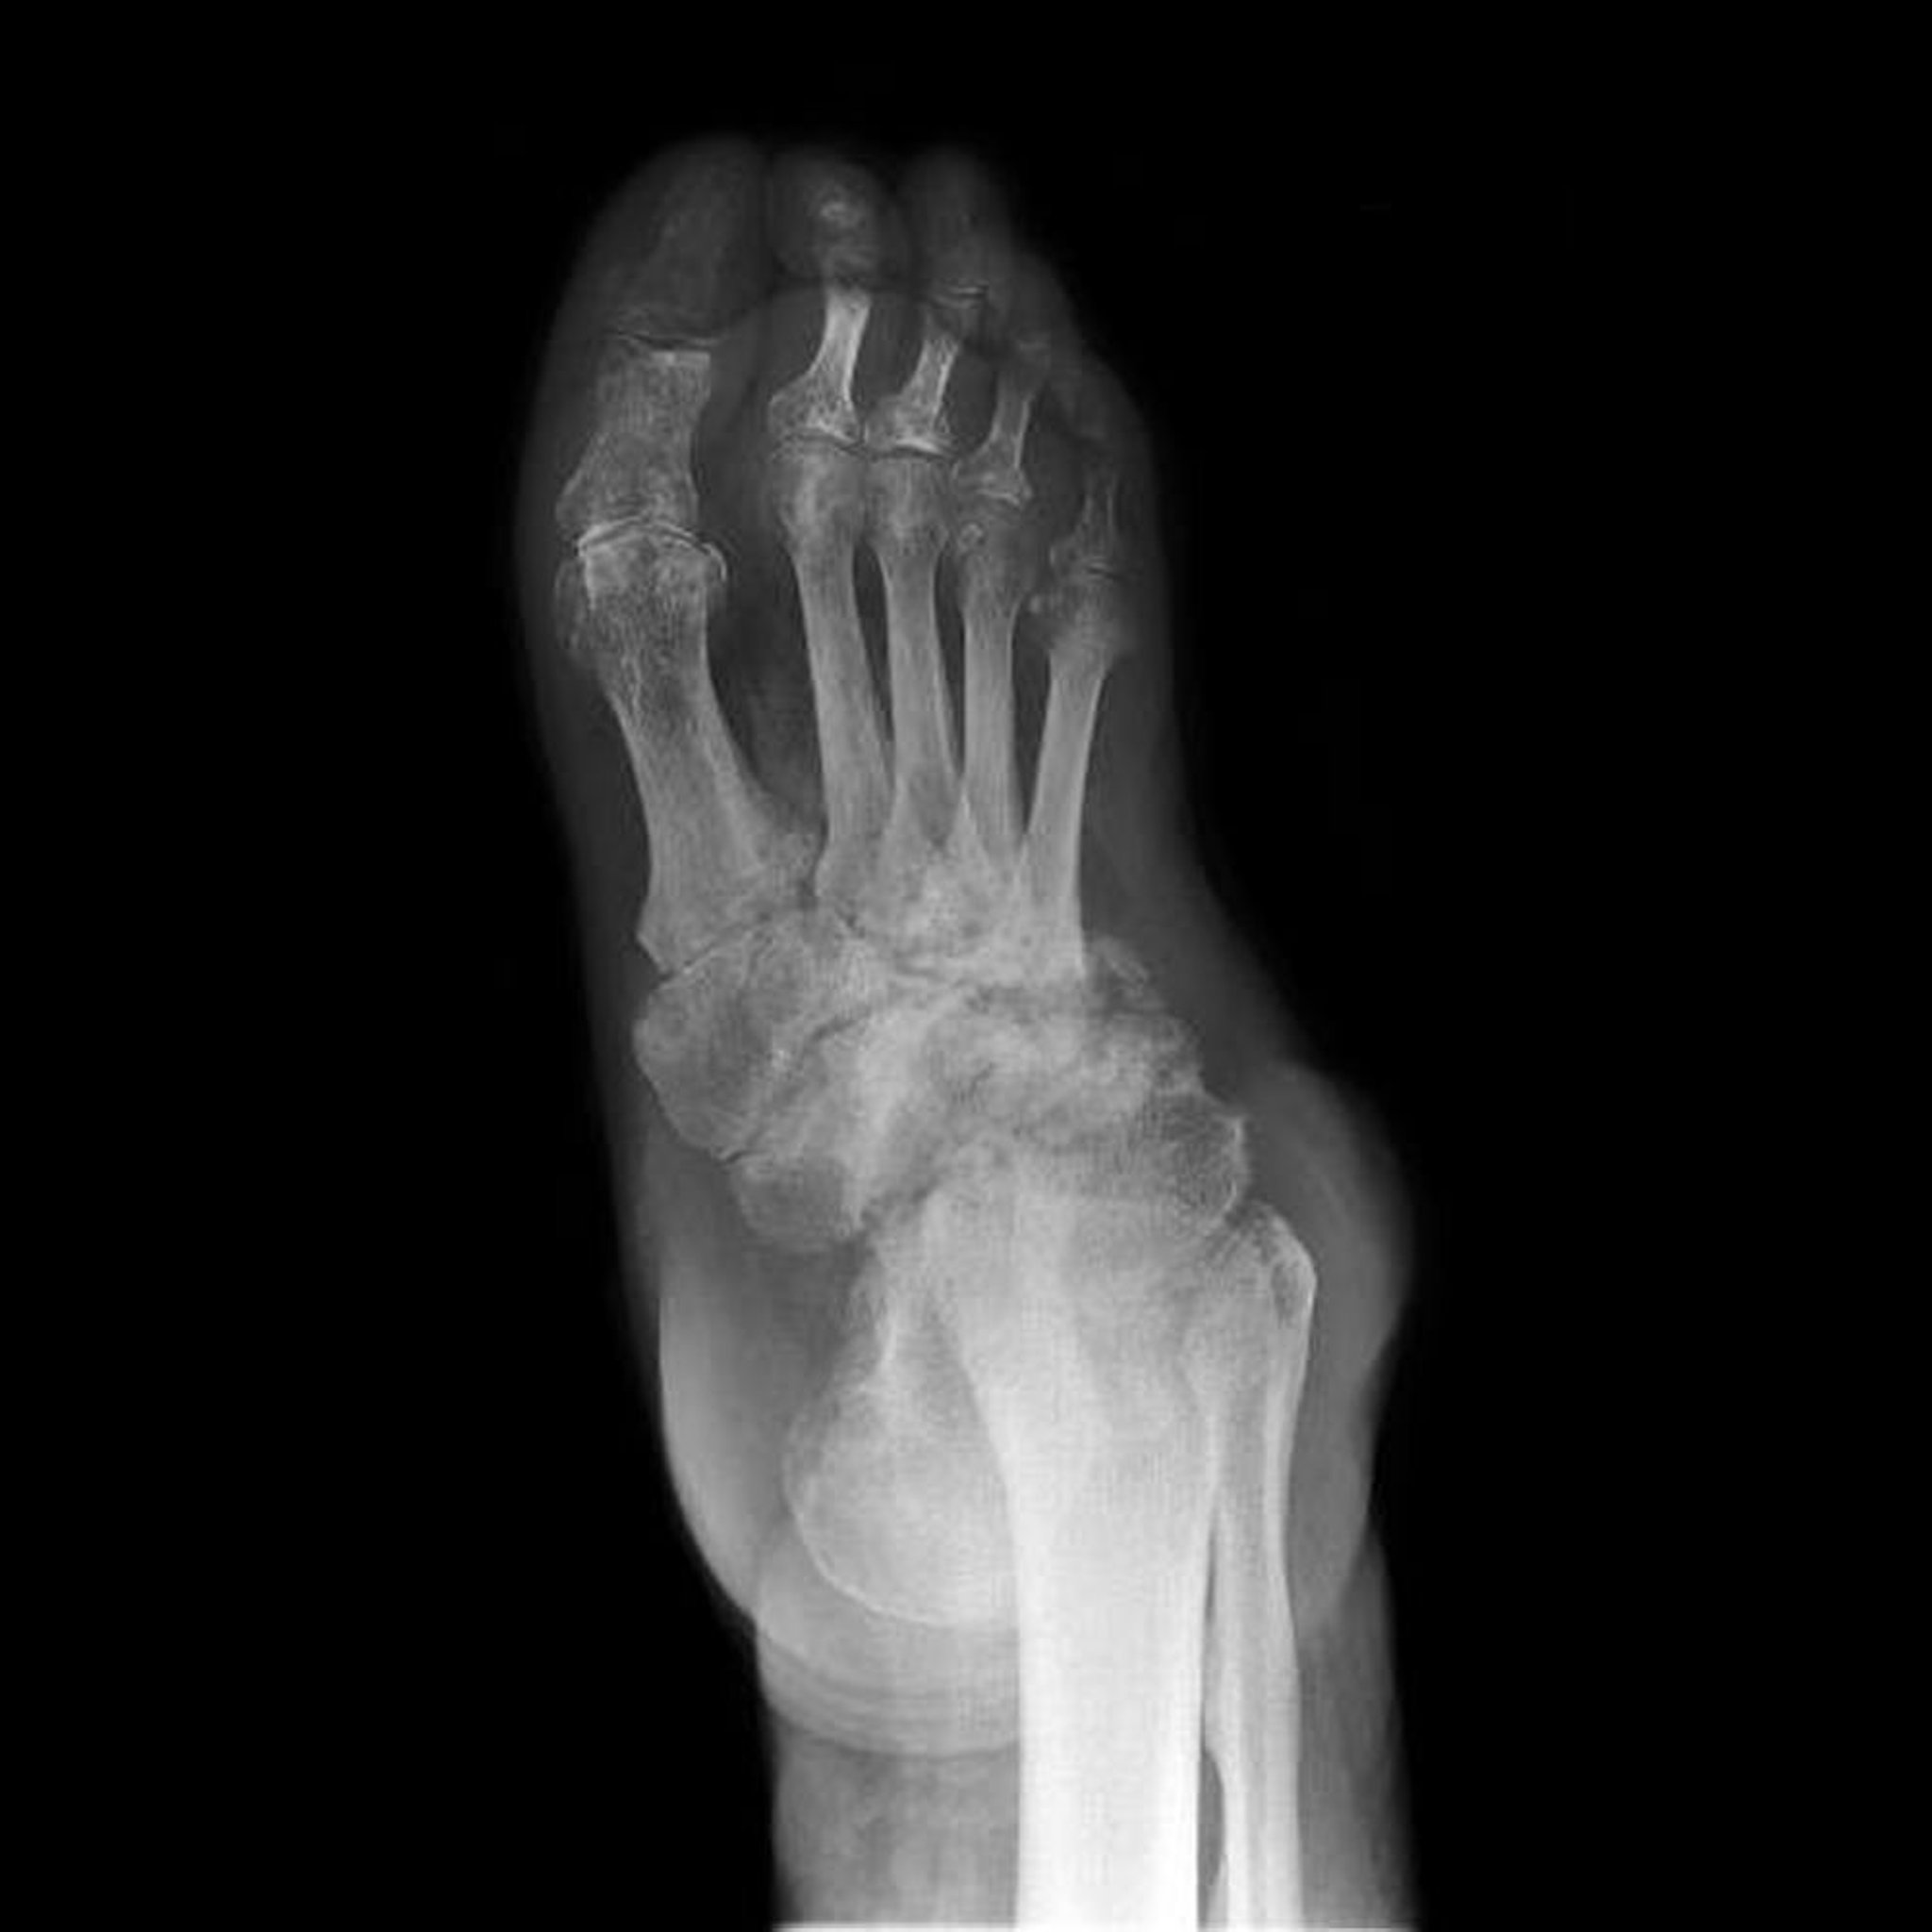

Artropatía neuropática del pie

Esta radiografía muestra una artropatía neuropática del pie (también conocida como pie de Charcot). La destrucción, las deformidades y la pérdida de los espacios articulares de los huesos del tarso son extensas.